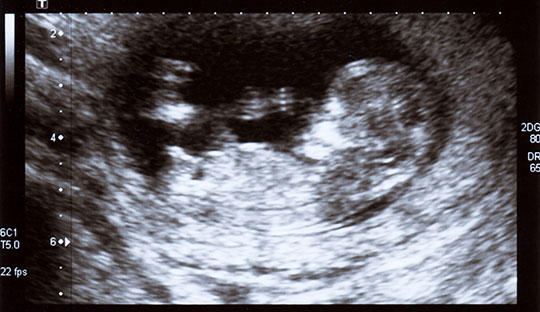

NT值是指颈项透明层厚度,是孕早期判断胎儿染色体异常的有效方法之一,用于评估唐氏综合征的风险。在上图的NT图示中,NT测查的则为胎儿颈后皮下组织内无回声带。正常情况下,在胚胎淋巴系统发育健全之前,少量淋巴液集中在颈部淋巴囊或淋巴管内,这就形成了透明层,也就是NT检查的依据。随着时间的增长,胎儿也随之增大,约14周后胚胎淋巴系统发育已接近完善,聚集的淋巴液会迅速引流至项内静脉,透明层就会消失,这时候再想通过NT检测排畸就不准确了。

NT检查图解